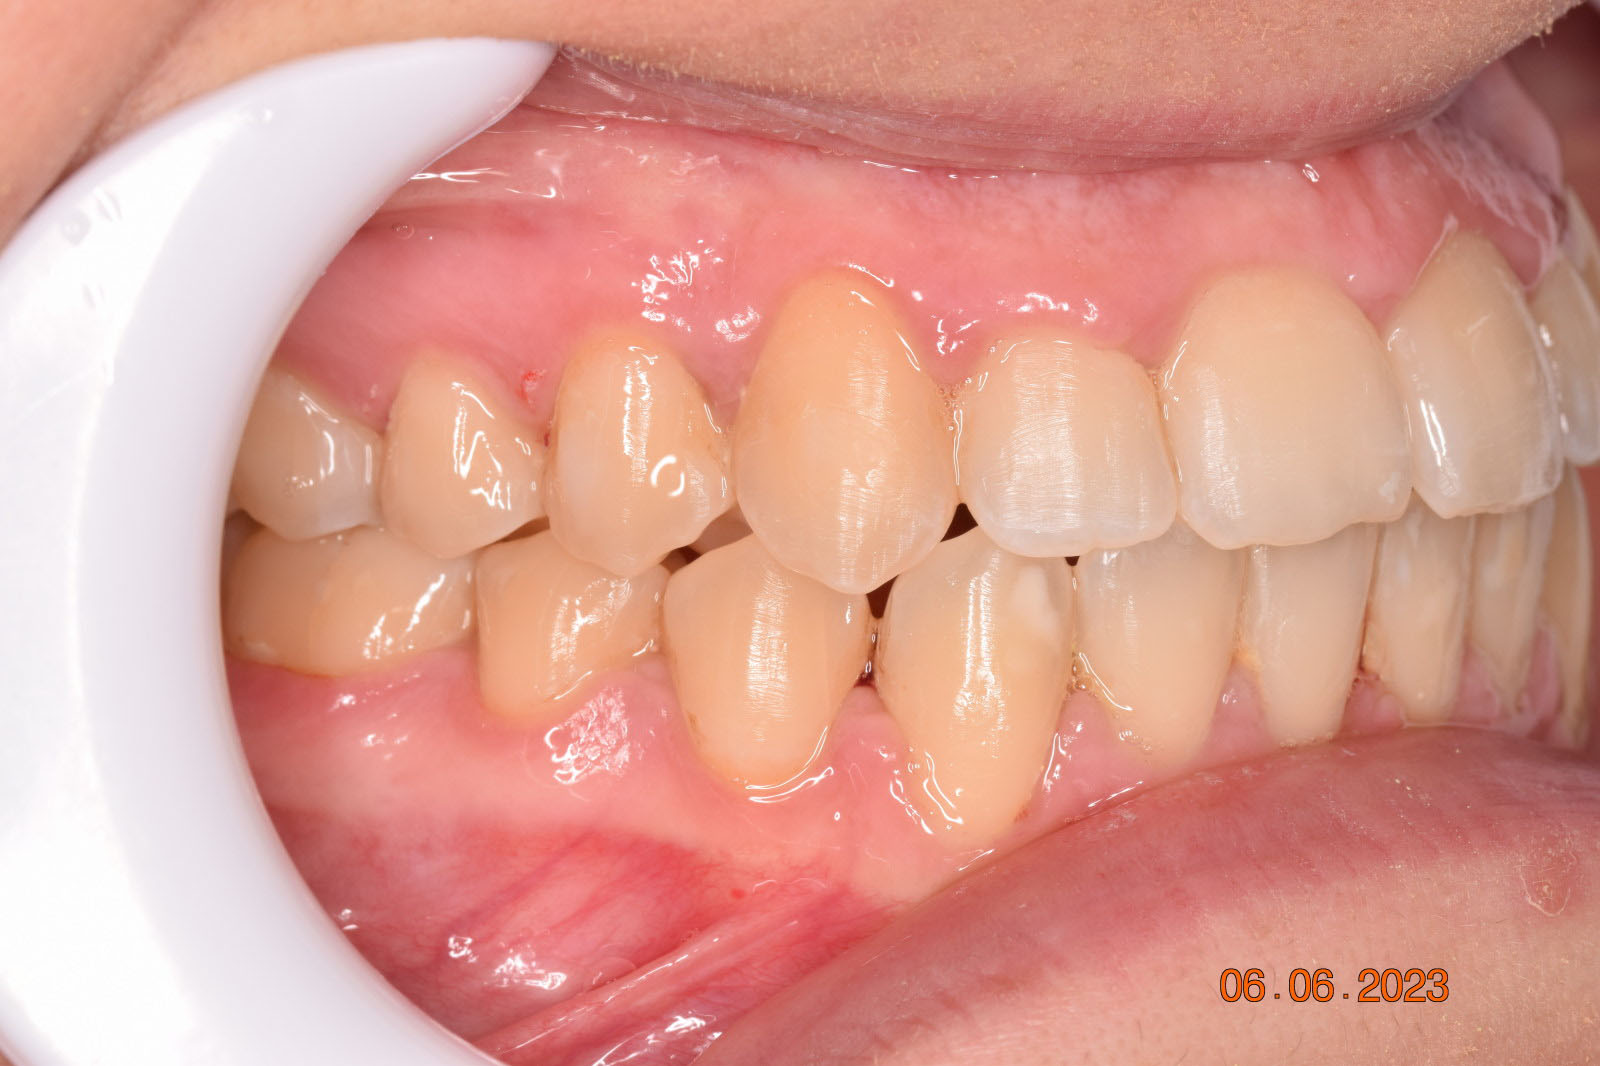

The teeth are in a very good position and the bone has reshaped.

This case posed challenges in all three spatial dimensions, compounded by significant crowding. The patient was highly compliant and maintained excellent oral hygiene throughout the 5.5 years of treatment, which required more than 30 clinical appointments.

The facial changes are impressive considering treatment involved only conventional orthodontics and not orthopedic interventions, TADs, or surgery.